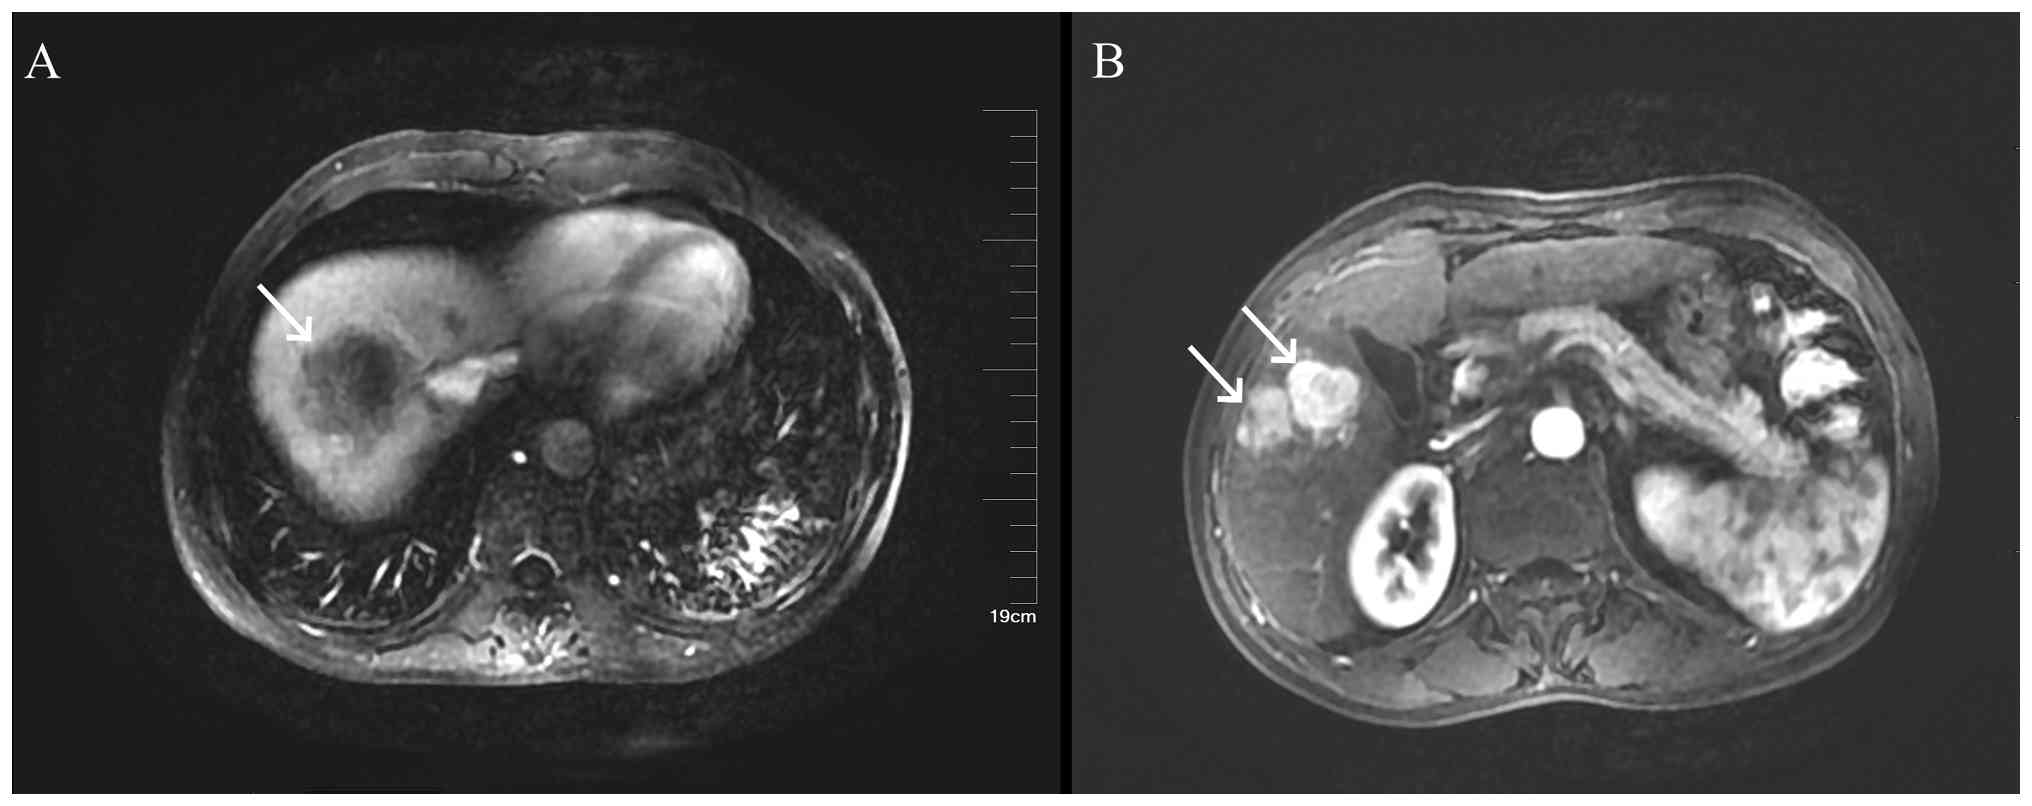

Ultrasound of the liver, gallbladder, pancreas, spleen and kidneys revealed a large solid mass in the liver (Fig. 1), a hypoechoic lesion between the upper pole of the right kidney and the posterior segment of the right lobe of the liver and a hypoechoic nodule in the first hepatic portal area. The liver ultrasound findings were consistent with chronic liver disease. An enhanced MRI of the liver suggested a high likelihood of hepatocellular carcinoma (HCC) in the right lobe (Fig. 2), with multiple metastatic tumors in the liver, bilateral adrenal glands and pancreas. A chest CT scan with three-dimensional reconstruction indicated a mass in the left hilum and left upper lobe of the lung, raising concerns for a malignant lesion with obstructive inflammation. The patient underwent ultrasound-guided biopsy of the liver mass and lymph nodes in the left supraclavicular region. Pathological examination (Fig. 3), supported by immunohistochemical staining performed according to the standard diagnostic protocols of the Department of Pathology at Hebei General Hospital, confirmed the diagnosis of SCNEC. Immunohistochemical staining (the full results are based on pathology reports rather than retrievable images, as the pathology reports cannot be published) included pan-cytokeratin (CKpan) (+), vimentin (−), chromogranin A (CgA) (+), synaptophysin (Syn) (+), cluster of differentiation 56 (CD56) (+), thyroid transcription factor-1 (TTF-1) (+), arginase-1 (−), hepatocyte paraffin 1 (HepPar-1) (−) and P53 (+++), and Ki-67 showing an active region of ~70% positive.

Case 1: Enhanced MRI of the liver. A

massive mass along with multiple small nodules was observed within

the right hepatic lobe, measuring ~13.7×12.6×11.4 cm.

Figure 2.

Case 1: Enhanced MRI of the liver. A massive mass along with multiple small nodules was observed within the right hepatic lobe, measuring ~13.7×12.6×11.4 cm.

Case 2: Enhanced MRI of the liver. (A)

A roundish mass (indicated by the white arrow) was identified in

segments VII and VIII of the liver, measuring ~4.9×4.6×3.6 cm. (B)

Multiple round-like masses were detected within the liver. The

largest one (indicated by the white arrow), measuring ~2.7 cm in

diameter, was located in segment V.

Figure 4.

Case 2: Enhanced MRI of the liver. (A) A roundish mass (indicated by the white arrow) was identified in segments VII and VIII of the liver, measuring ~4.9×4.6×3.6 cm. (B) Multiple round-like masses were detected within the liver. The largest one (indicated by the white arrow), measuring ~2.7 cm in diameter, was located in segment V.